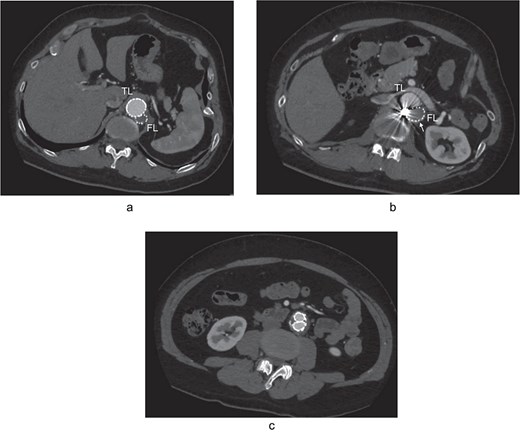

At 2-year post-procedure, CT follow-up showed AAA expansion to 56 mm, and FL dilation to 25 mm. The contrasted CT showed small inflow to the FL from the TL through the gap between the intimal flap and the FL stent graft via a residual intimal tear, as well as reversal flow from re-entry at the EIA (Fig. 2a–c). A second-stage endovascular repair was planned for completing the TAAA repair. Under local anesthesia, the gap between the FL stent graft and the intimal flap was occluded using DELTAFIL (Jonson & Jonson, NJ, USA) from FL side to close a residual intimal tear (Fig. 2d). The eighth intercostal artery and the third lumbar artery were occluded using DELTAFIL and GARAXY G3 (Jonson & Jonson, NJ, USA), respectively to block the backflow from these side branches. Then the 8 × 59 mm VBX (WL Gore & Associates, Newark, DE, USA) was deployed at left EIA covering the re-entry tear, successfully completing FL closure (Fig. 2e). The postoperative course was uneventful, with no paraplegia, and he was discharged on the postoperative day 4. The postoperative contrast-enhanced CT showed no contrast inflow into the FL. The CT imaging 3 years after the procedure showed the reduced diameter of abdominal aorta of 35 mm (Fig. 3a–c).

The postoperative contrast-enhanced CT axial images 3 years after the procedure showed no contrast inflow into the FL, and the reduced diameter of post-dissection thoracoabdominal aortic aneurysm at thoracic level (a), renal artery level with FL stent graft (b; white arrow), and abdominal level (c). TL: true lumen; FL: false lumen.